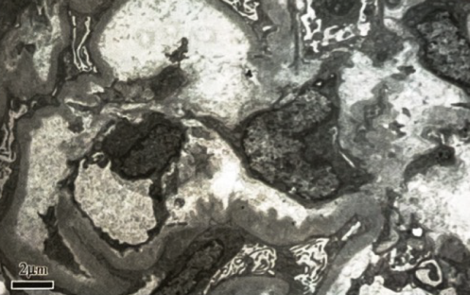

患者于入院第4天行肾穿刺活检。免疫荧光:IgG(++),C3(++),颗粒样毛细血管壁、系膜区沉积。光镜(图1):可见34个肾小球,肾小球系膜细胞和内皮细胞弥漫增生,白细胞浸润,基底膜增厚,部分缺血性皱缩,系膜区、上皮下、内皮下嗜复红蛋白沉积,局灶节段性微血栓及白金耳形成,部分缺血性皱缩;肾小管上皮细胞空泡及颗粒变性,局状及片状萎缩,肾间质灶状及片状淋巴和单核细胞浸润;小动脉管壁增厚,内膜肿胀伴血栓形成。该表现符合毛细血管内增生性狼疮肾炎伴基底膜增厚[Ⅳ-G(A)+V]伴血栓性微血管病(TMA)。

图1.光镜表现